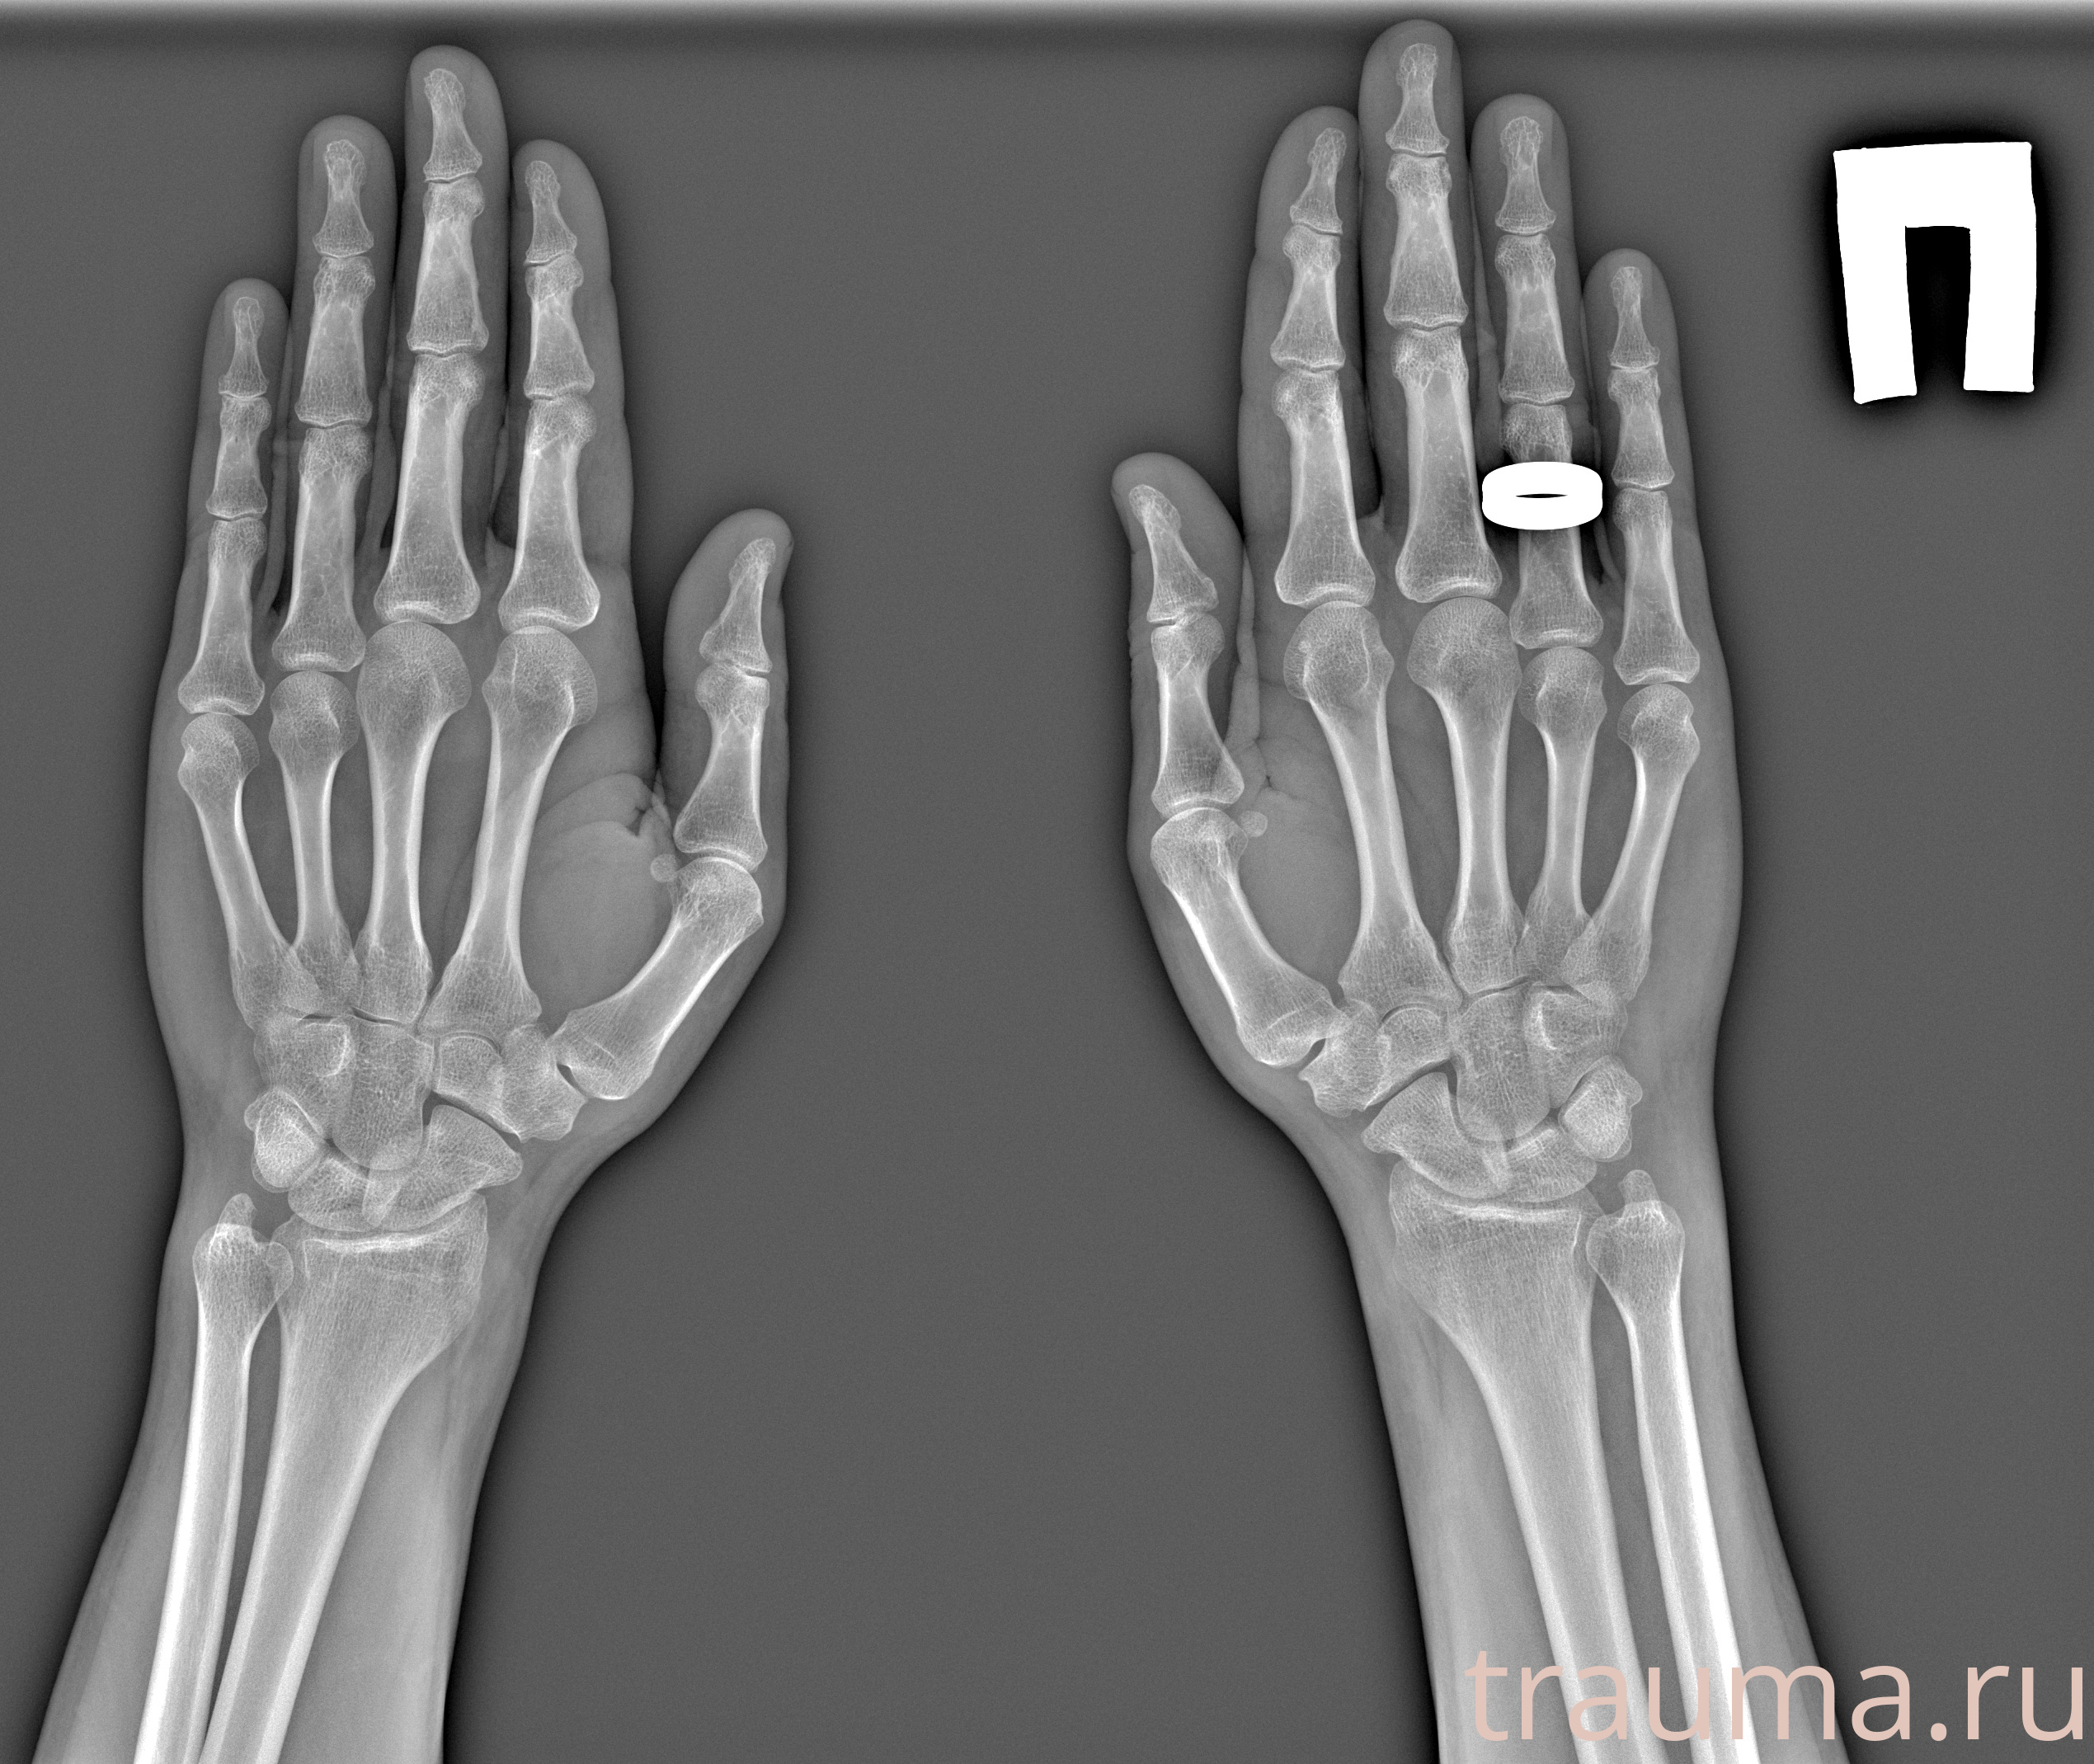

Рентген на дому: по вашему адресу приезжает врач-рентгенолог, травматолог-ортопед с мобильным рентгеновским аппаратом, проводит диагностику травмы или заболевания, делает необходимые рентгенограммы, дает рекомендации по дальнейшему лечению. Получить качественные снимки в домашних условиях возможно благодаря уникальной методике, разработанной МосРентген Центром для института  Склифосовского